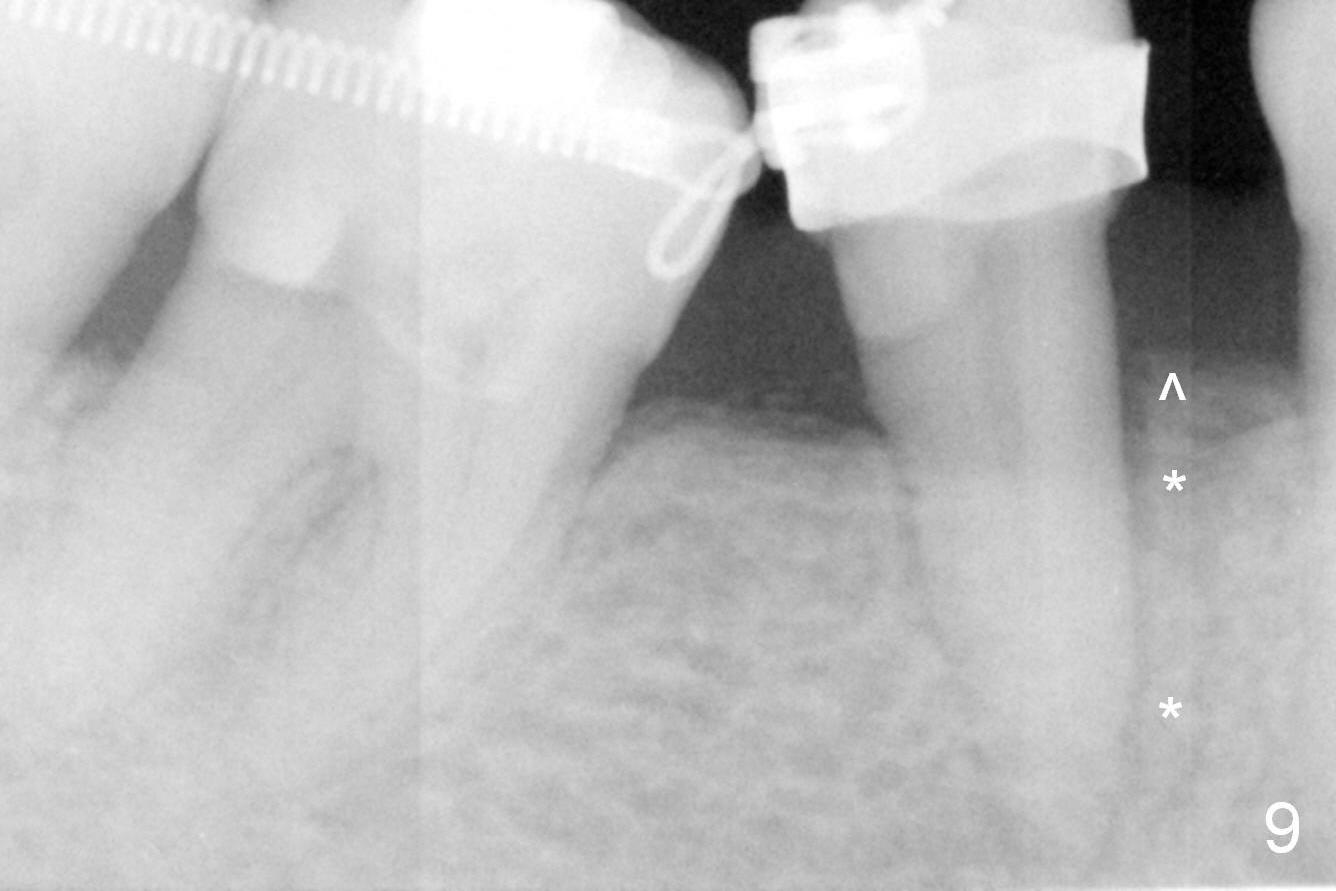

A 47-year-old lady has lost the lower right 1st molar for long time; with reduction of the buccolingual width (Fig.1) and mesiodistal width (Fig.2,3). With regional orthodontic appliance (Fig.4) for 3 months, the tooth #29 has started being distalized (Fig.5). One month and a half later, the tooth #26 starts to shift labially. Power chains and then closed coil spring are placed between #29 and 32. #29 distalization is slow (Fig.7) with closure of the diastema between #31 and 32 (Fig.8, as compared to Fig.1,3). Seven months post banding, a 10 mm miniimplant is placed distobuccal to the tooth #32 (Fig.6); the same 12-mm closed spring is stretched distal by ~ 6 mm (Fig.8 between arrowheads). Two months later, #29 is more distalized (Fig.9 tilted) with bone deposit mesially (*) and coronally (^). A .018' stainless steel wire is installed with an open coil spring placed between #28 and 29 (Fig.10 (^),11). Note #29 rotation (Fig.11). To solve the tilting, a power hook (Fig.12 black) will be clamped to a .016x.016 wire (red), while the closed spring is lowered and attached to the power hook (Fig.12 white). Take photos after removing the existing wire occlusally to show the alveolar width change. When the wire is placed, make sure that the distal wings of #29 bracket is fully engaged to reduce the tooth rotation. Make occlusal adjustment on #31 and 32 to reduce anterior open bite.